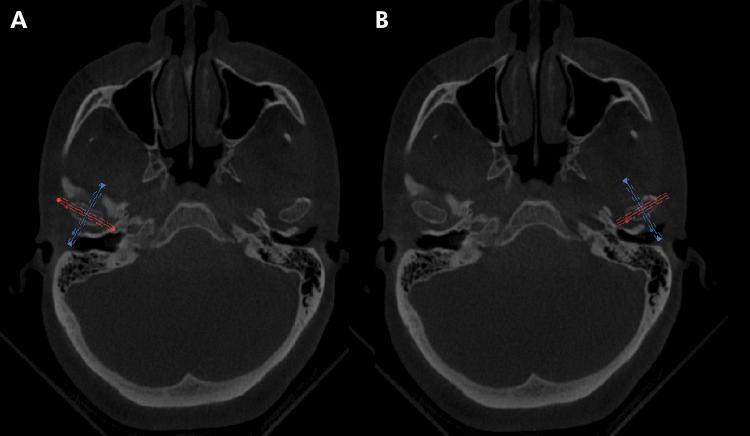

This observational, cross-sectional study with retrospective collection was aimed to evaluate the prevalence of morphological changes in mandibular condyles in individuals with class II malocclusion, classified according to different vertical growth patterns (brachyfacial, mesofacial, and dolichofacial), through cone beam computed tomography (CBCT). Seventy CBCT images (140 mandibular condyles) were selected from individuals without orthodontic treatment, of both sexes, aged between 25 and 50 years. No statistically significant differences were found between facial patterns; however, there was a higher relative prevalence of bone changes in dolichofacial individuals with flattening (62%), sclerosis (44%), and subchondral bone cyst (20%). Erosion and osteophytes prevailed in mesofacial (39%), and brachyfacial individuals (32%), respectively. Thus, there was no statistically significant difference in the prevalence of degenerative changes between the vertical skeletal patterns. Flattening was the most prevalent change, whereas subchondral bone cyst was the least prevalent among the three groups studied. The observational design of this study makes it possible to analyze image banks to verify the correlation of morphological changes in the temporomandibular joint in different facial patterns in patients with class II malocclusion. A limitation of the study is that clinical characteristics were not evaluated.

这项采用回顾性收集数据的观察性横断面研究旨在通过锥形束计算机断层扫描(CBCT)评估安氏II类错牙合个体中,根据不同垂直生长模式(短面型、平均面型和长面型)分类的下颌髁突形态变化的患病率。从年龄在25至50岁之间、未经正畸治疗的男女个体中选取了70张CBCT图像(140个下颌髁突)。面部模式之间未发现统计学上的显著差异;然而,长面型个体中出现骨质改变(变平占62%、硬化占44%、软骨下骨囊肿占20%)的相对患病率较高。侵蚀和骨赘分别在平均面型个体(占39%)和短面型个体(占32%)中更为常见。因此,垂直骨骼模式之间退行性改变的患病率没有统计学上的显著差异。变平是最常见的改变,而软骨下骨囊肿是所研究的三组中最不常见的。本研究的观察性设计使得分析图像库以验证安氏II类错牙合患者不同面部模式下颞下颌关节形态变化的相关性成为可能。该研究的一个局限性是未评估临床特征。